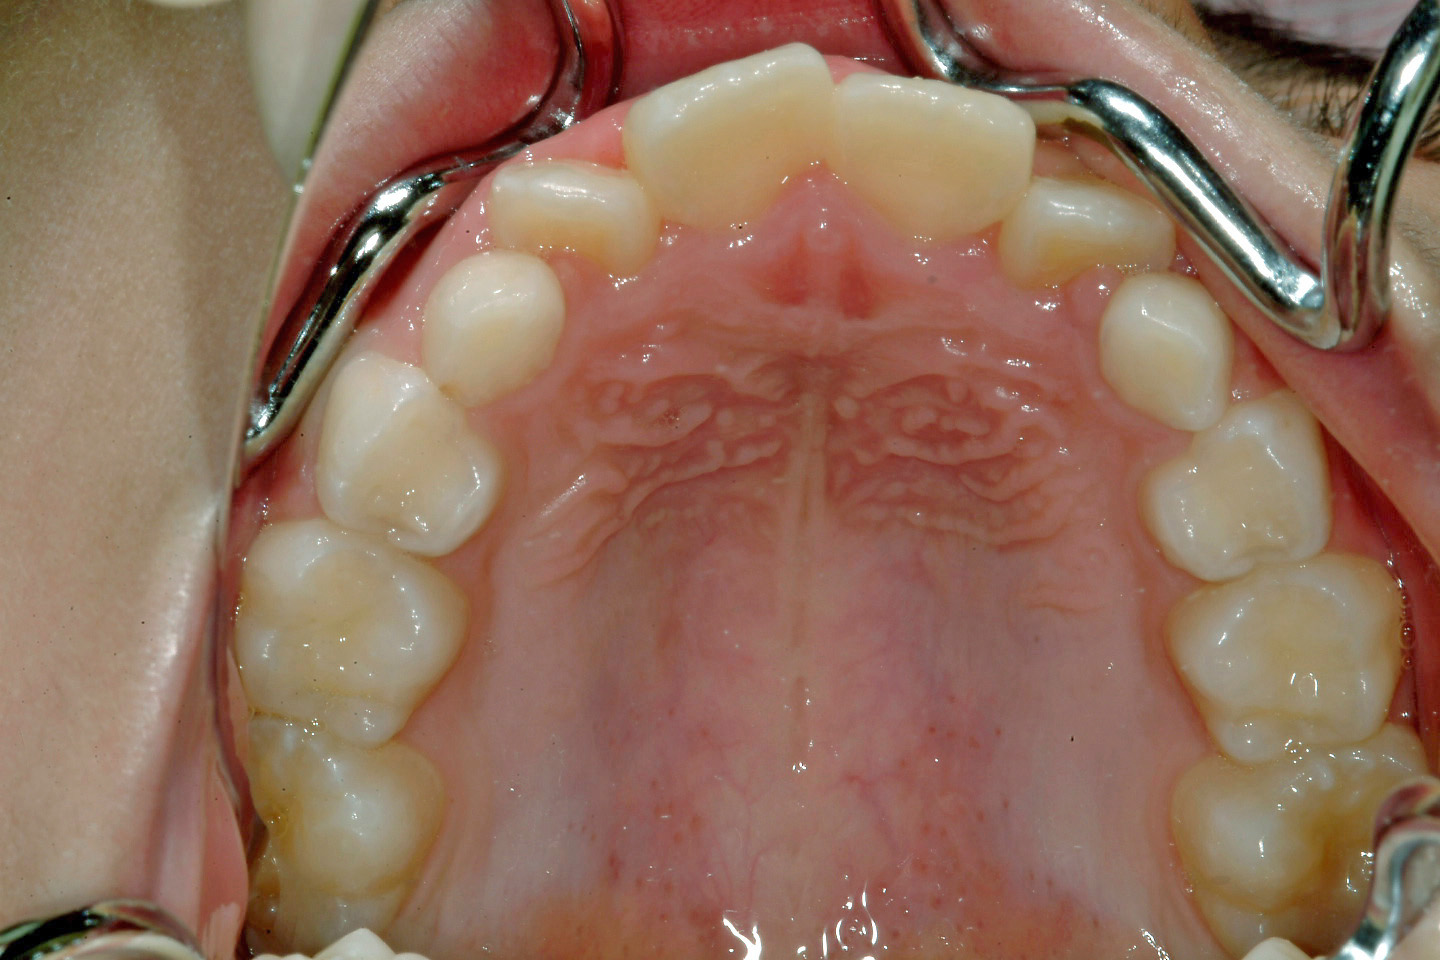

上顎前突(出っ歯)

叢生(乱ぐい歯)

出っ歯を気にされて来院された7歳の男子です。永久歯の並ぶ空隙がほとんどなく、このままでは重度の叢生が予想される状態でした。そのため、ヘッドギアーによる上顎大臼歯の遠心移動と上下顎の拡大を前期治療として行いデーモンシステムを用いたエッジワイズ治療に移行いたしました。患者さんの協力もよく非抜歯での配列することができました。動的治療後にボンデッドワイヤーとリテーナーを併用した保定に移行しております。